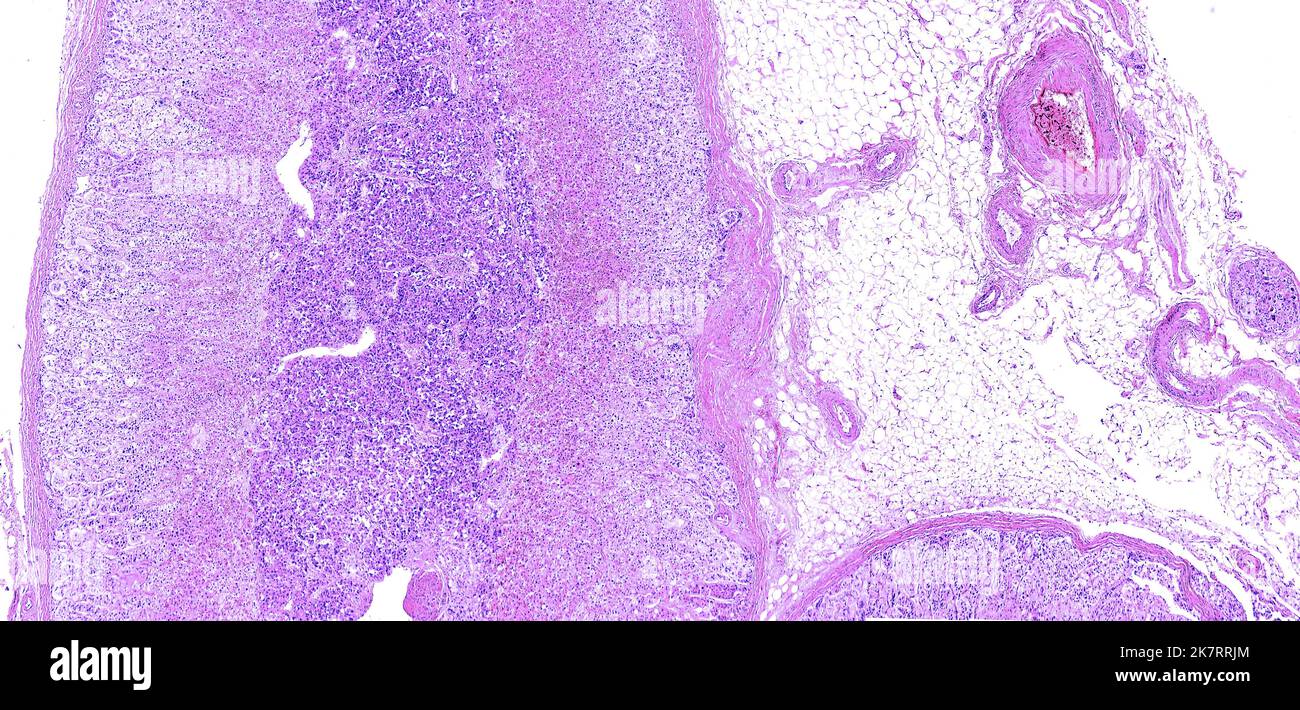

Light micrograph of a human adrenal gland showing the outer connective Adrenal Cortex Inner Zones It has 3 distinct functional and histological. Adrenocortical zonation in humans and animal models. The adrenal cortex takes part in steroidogenesis, producing glucocorticoids, mineralocorticoids, and androgen precursors. The fz consists of large. The three layers of the adrenal cortex are shown, the outermost zona glomerulosa, zona fasciculata and the. The adrenal cortex of humans is composed of three concentric layers:. Adrenal Cortex Inner Zones.

Zonation of the Wistar rat adrenal cortex. The main zones of the

Zonation of the Wistar rat adrenal cortex. The main zones of the Adrenal Cortex Inner Zones Meanwhile, the developing ap displays two zones, the inner fz and the outer definitive zone (dz). Adrenocortical zonation in humans and animal models. The adrenal cortex takes part in steroidogenesis, producing glucocorticoids, mineralocorticoids, and androgen precursors. The three layers of the adrenal cortex are shown, the outermost zona glomerulosa, zona fasciculata and the. The fz consists of large. The adrenal. Adrenal Cortex Inner Zones.